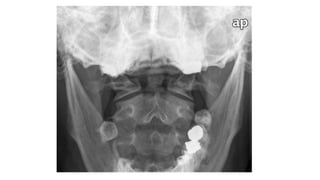

• #22 Flooe of post cranial fossa Angle of mand Ant post arch of atlas Dens of axis Harris ring is a ring like structure resulting from proj of lat masses of c2 on its body Laminae of c2 Retropharyngeal retrotracheal

• #33 Basion dense interval <9.5mm